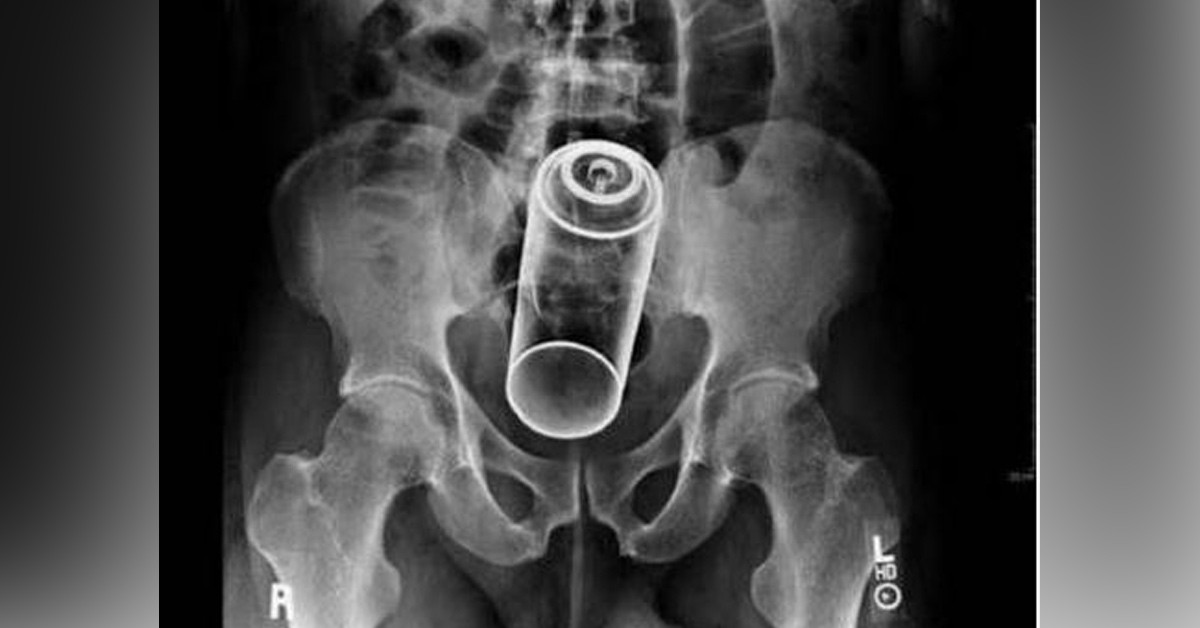

Gerçek mi bu ya!